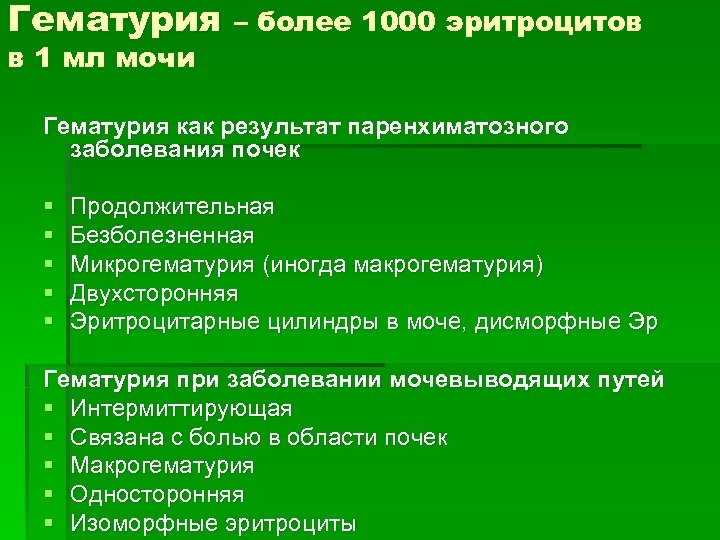

Гематурия – более 1000 эритроцитов в 1 мл мочи Гематурия как результат паренхиматозного заболевания почек § § § Продолжительная Безболезненная Микрогематурия (иногда макрогематурия) Двухсторонняя Эритроцитарные цилиндры в моче, дисморфные Эр Гематурия при заболевании мочевыводящих путей § Интермиттирующая § Связана с болью в области почек § Макрогематурия § Односторонняя § Изоморфные эритроциты